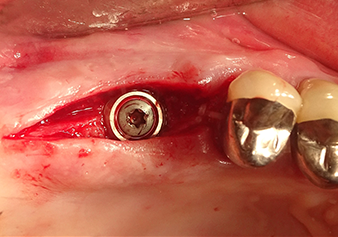

Preparazione e accrescimento della sede dell'impianto

Dopo un controllo intermedio (Fig. 4) è stata eseguita un'ulteriore fase di preparazione (Fig. 5). Lo strumento idraulico Z35P è stato utilizzato in un secondo momento per sollevare la membrana sino alla posizione desiderata (Fig. 6 e 7). In seguito alla suddetta operazione, si è proceduto ad una ulteriore preparazione piezochirurgica della sede dell'impianto conclusasi con l'applicazione della fresa e della fresa a spallamento sul diametro dell'impianto di 4,8 mm. Il materiale di rinforzo (dimensione delle particelle di ca. 0,8 - 1,6 mm) è stato introdotto sotto la membrana di Schneider prima che venisse inserito l'impianto (Fig. 8).